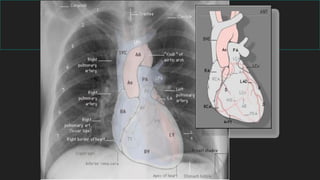

4- Mediastino

- Región situada centralmente

- Límites son:

opérculo torácico (sup.)

diafragma (inf.)

esternón (ant.)

columna vertebral (post.)

BORDE DERECHO

TVBD

VCS

Ao ascendente

TVBDAo ascendente

Aurícula derecha

BORDE IZQUIERDO

TVBI Art.

Subclavia

Botón aórticoTronco de la arteria

pulmonar

Cayado

aórtico

Tronco de la

art. pulmonar

Orejuela de la

aurícula izquierda

Orejuela

aurícula

izquierda

Ventrículo izquierdo

Ventrículo

izquierdo

Radiología de tórax normal

CORRELACIÓN TOPOGRAFICA

MEDIASTINAL / RX TORAX

BORDE ANTERIOR

Ventrículo derechoTronco de la arteria

AortaAurícula izquierdaVCI

BORDE POSTERIOR

ÍNDICE

CARDIOTORÁCICO

Ǿ transverso > tórax

Ǿ transverso > corazón

Normal = < 0,5

PROMINENCIA BOTÓN

< 3 cm

Rx Torax A/P

0,5

DIAMETRO TRANVERSO

MAXIMO CORAZON

DIAMETRO

TRANSVERSO MAXIMO

TORAX